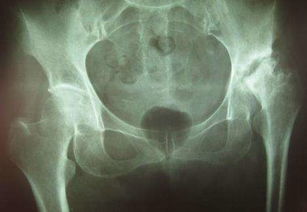

我們分析一下股骨頭壞死。現(xiàn)在的股骨頭壞死主要是缺血性無菌型股骨頭壞死,通常簡稱股骨頭壞死。這種股骨頭壞死,是因為血管堵塞、股骨頭的骨細胞缺氧、缺水、缺營養(yǎng)紛紛死亡,所謂的“股骨頭壞死”并不是股骨頭里所有的骨細胞都死光光。事實上,即使是壞死很嚴重的股骨頭里面,都或多或少存在著活的骨細胞,要不然股骨頭早就萎縮消失了。因此,只要恢復(fù)向股骨頭供血,那些活著的骨細胞就因為得到更多的氧氣、水和營養(yǎng),就能夠進行高速度的細胞分裂,實現(xiàn)包括骨細胞、各種軟組織細胞在內(nèi)的細胞大量增殖(這和“有了充足的磚瓦水泥鋼材等,就可以建起大量樓房”一個道理)。

股骨頭壞死,又稱股骨頭缺血性壞死,為常見的骨關(guān)節(jié)病之一。

大多因風(fēng)濕病、血液病、潛水病、燒傷等疾患引起。至于它用什么方法治療比較好,這要看而定者的股骨頭的塌陷程度。